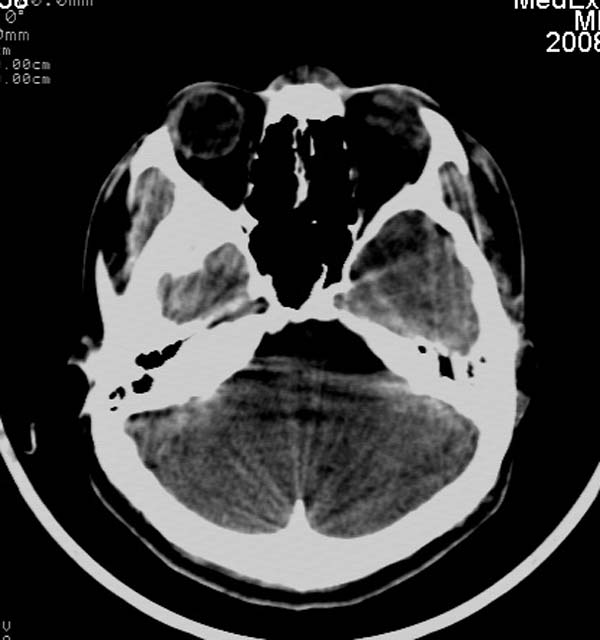

患者,男,24岁。头面部外伤后意识障碍1小时。

小脑幕缘密度增高,考虑有少量出血,建议复查

考虑右侧天幕缘少量蛛网膜下腔出血;建议:必要时复查。

1)考虑少量蛛网膜下腔出血;建议:必要时复查。2)桥前池及左侧环池表皮样囊肿可能。建议:行mri检查。

1)考虑蛛网膜下腔出血;建议:复查。2)桥前池及左侧环池表皮样囊肿可能。建议:行mri检查。

考虑右侧天幕缘区域少量蛛网膜下腔出血。

当ct表现不明显,临床症状相当明显时,建议mri+dwi序列除外弥漫性轴索损伤之可能。

一侧密度增高,是否考虑为硬膜下血肿,前额血肿真好对冲伤,桥小脑脚增宽建议进一步检查